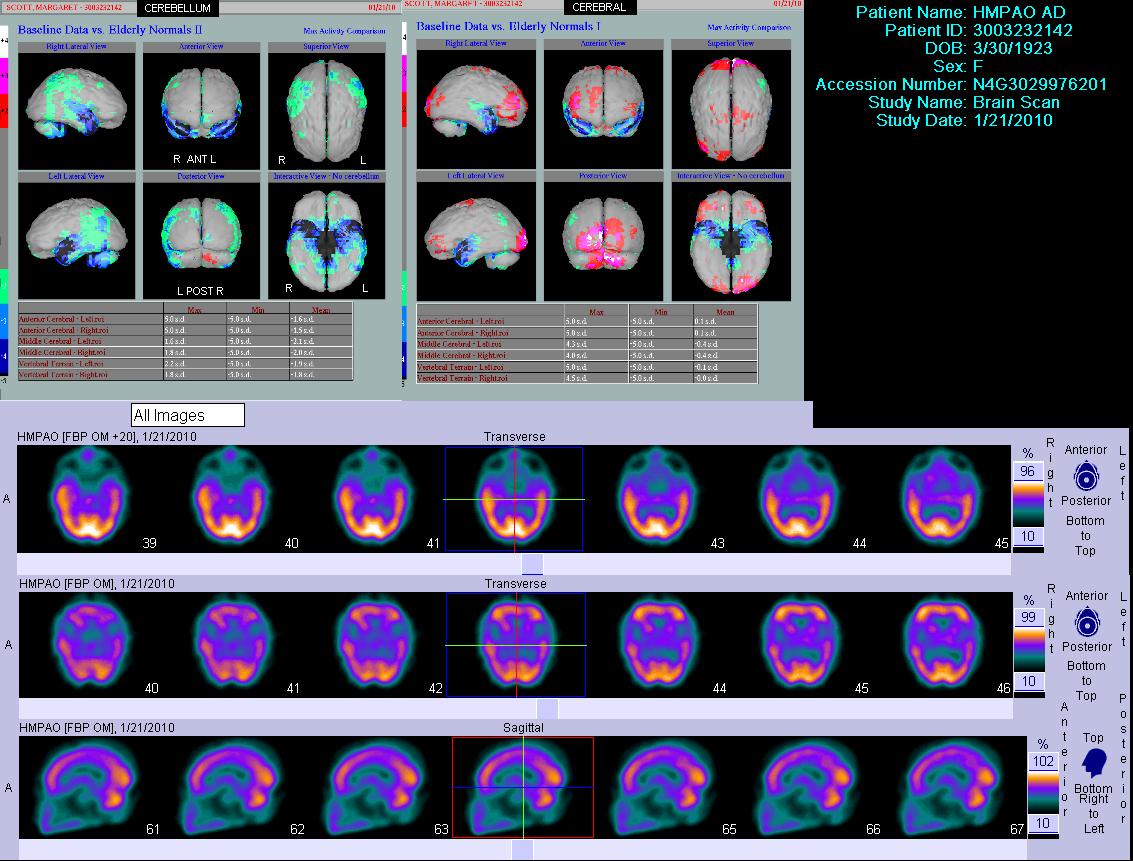

- Second, ACTRA aims to use innovative and advanced imaging techniques to better understand the link between cardiovascular risk, neurophysiology, and imaging markers of brain structure and function, and dementia related neuropathology cognitive decline as part of vascular and Alzheimer's dementia. For example, some of the projects will focus on cardiovascular and cerebrovascular link through neuroimaging methods such as MRI, SPECT (see figure below) and PET as well as researching the best methods of image analysis and of modelling imaging and other data.